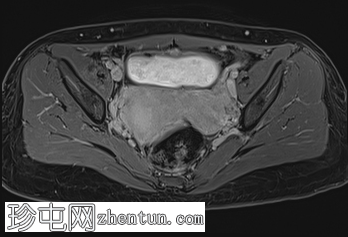

轴向位

T1

轴向 T1

脂肪饱和度

C+脂肪饱和度

盆腔增强 MRI 检查增强了我们对 CT 扫描中发现的病变的理解。右肾发育不全,左肾肥大伴肾积水,双子宫完整,阴道隔膜,发育不全侧阴道积血。

双侧卵巢均有多个功能性囊肿,右侧卵巢可见黄体囊肿。

CT和MRI检查结果为Herlyn-Werner-Wunderlich综合征的典型表现,其特征为经典的三联征:III型苗勒氏管异常(完全性双子宫)、中肾管异常(肾发育不全)以及肾发育不全侧阴道积血。